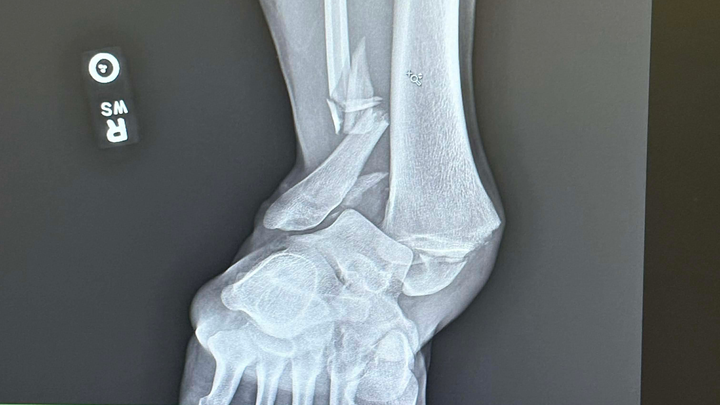

Ended up losing traction while driving in the snow and hit a tree. I broke my tibia, fibula, and ankle bone, gashed my eyebrow open (needed six stitches), broke some ribs, and bruised both lungs.